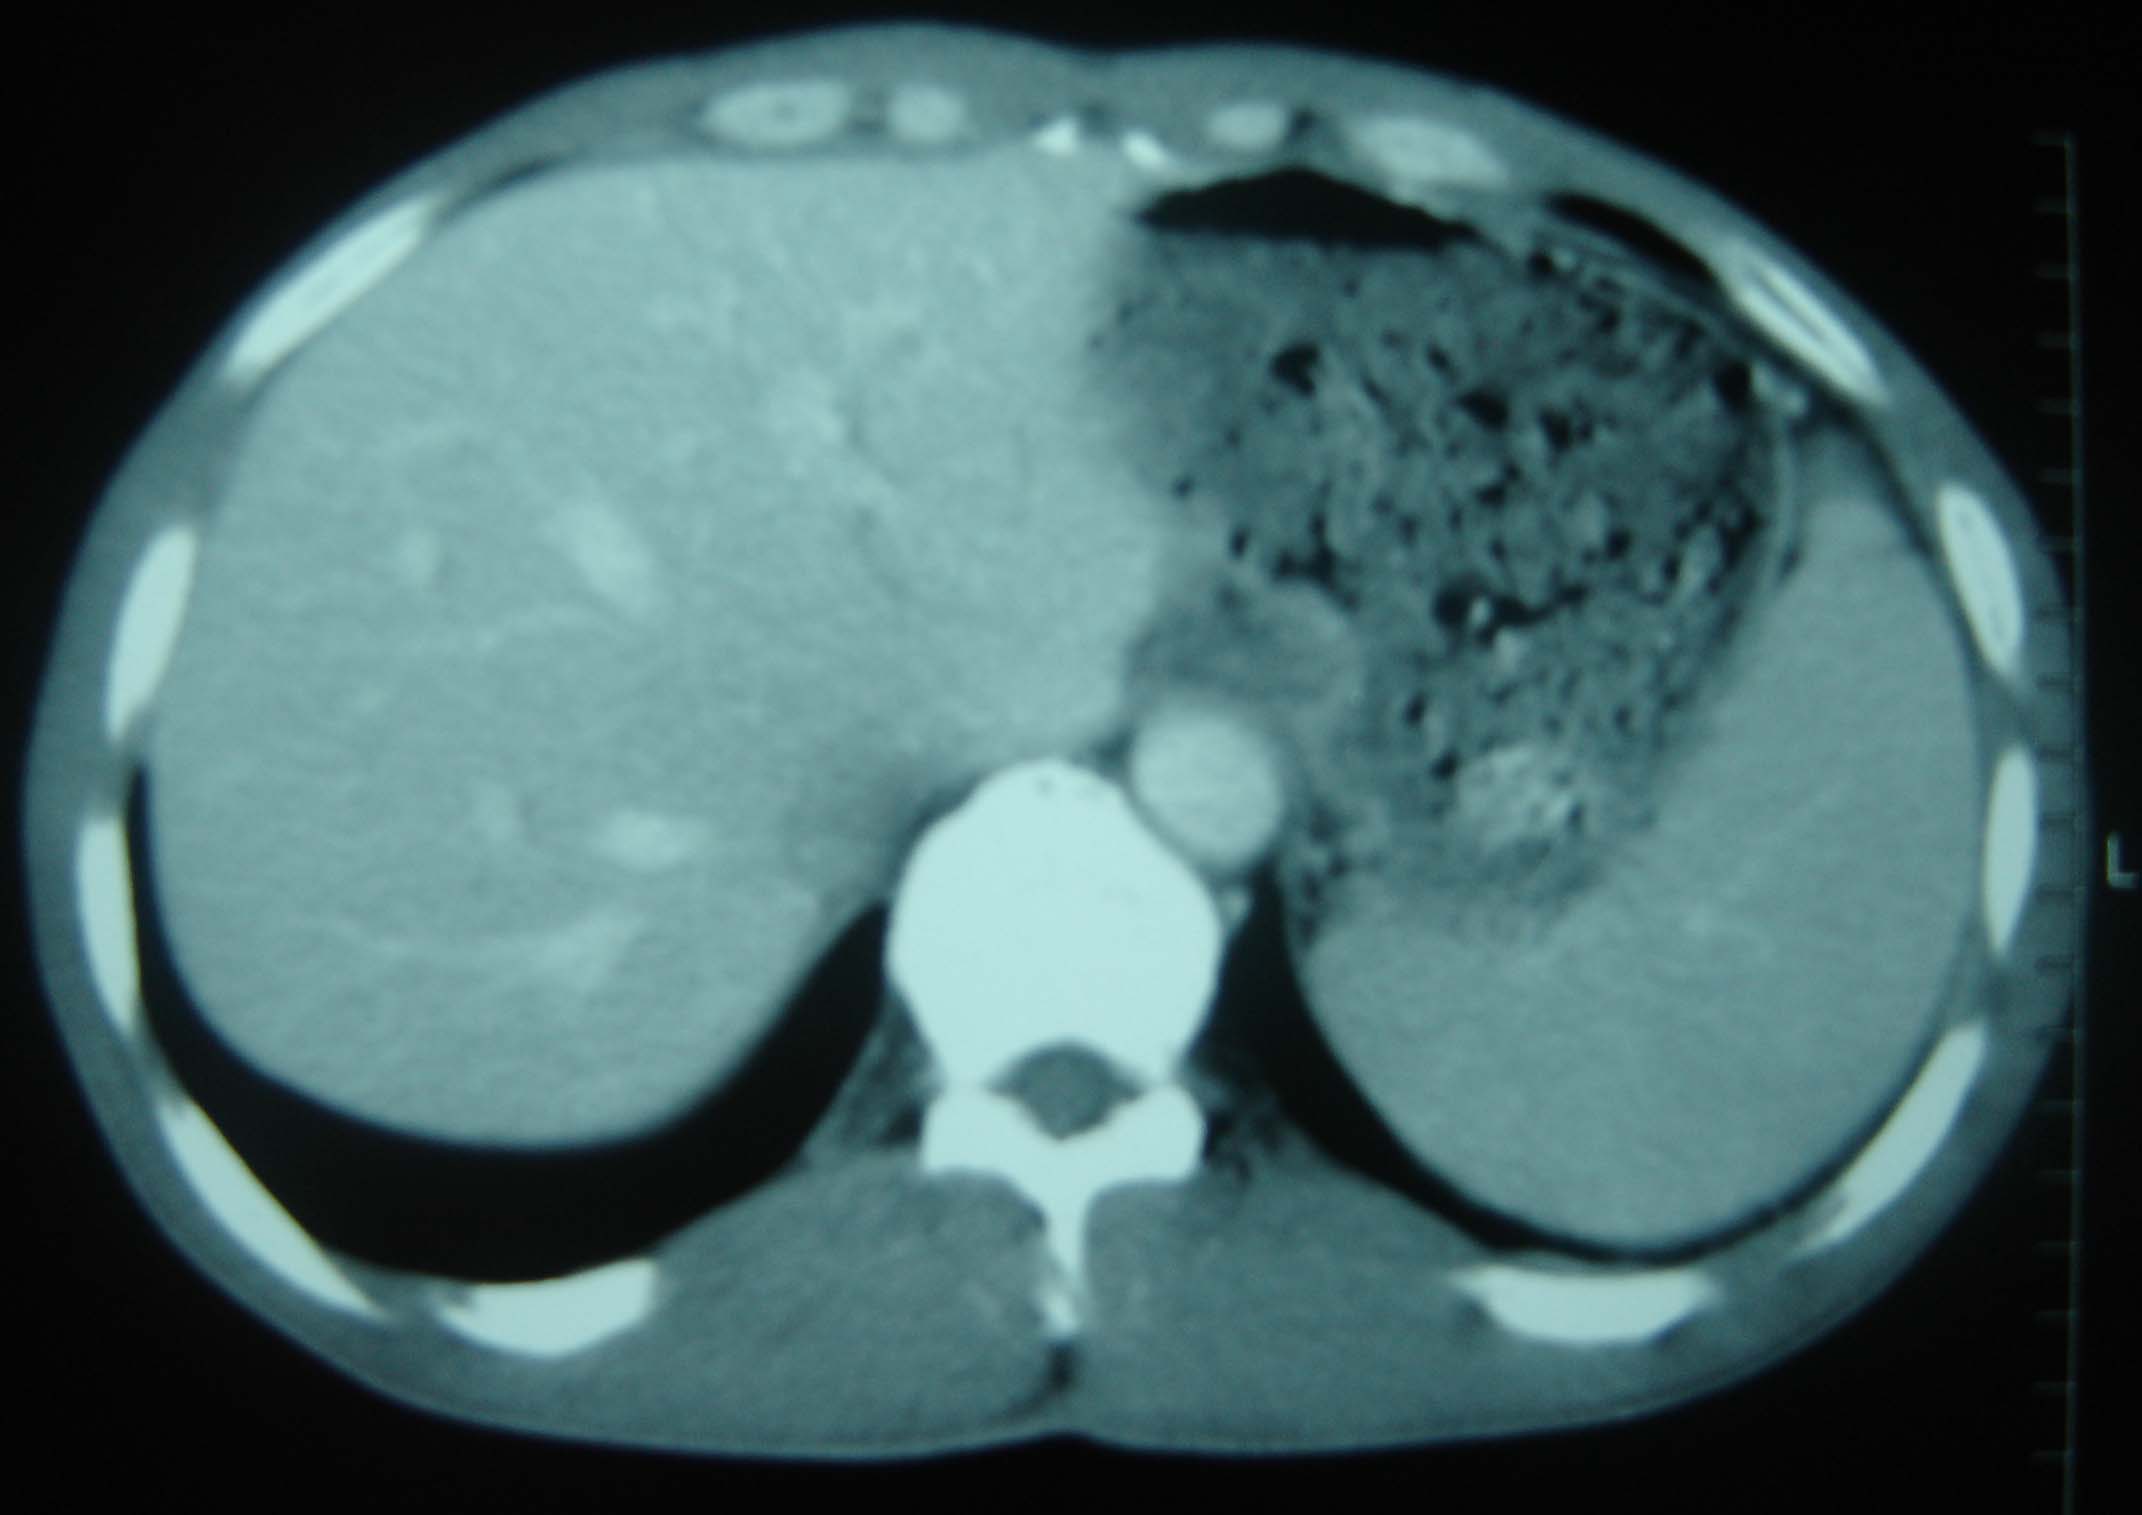

标题: CT25321:两肺多发结节 请会诊 [打印本页]

标题: CT25321:两肺多发结节 请会诊

男 、43岁,咳嗽胸痛,装修工,平时接触粉尘较多,有吸烟史10多年,纤维支气管镜检查未发现异常,胃镜、腹部b超检查亦未发现异常,颈部淋巴结活检未发现肿瘤细胞。

不能排除转移,如果不能找到原发灶,只有短期随访。

结节病?转移瘤?

1)考虑双肺及胸膜多发性转移瘤。2)肺气肿。